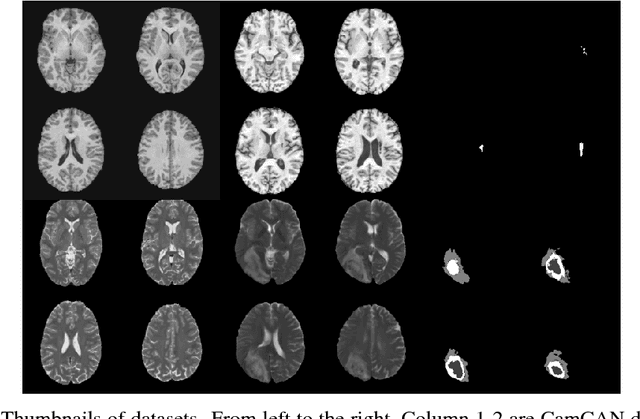

Recent advances in deep learning led to novel generative modeling techniques that achieve unprecedented quality in generated samples and performance in learning complex distributions in imaging data. These new models in medical image computing have important applications that form clinically relevant and very challenging unsupervised learning problems. In this paper, we explore the feasibility of using state-of-the-art auto-encoder-based deep generative models, such as variational and adversarial auto-encoders, for one such task: abnormality detection in medical imaging. We utilize typical, publicly available datasets with brain scans from healthy subjects and patients with stroke lesions and brain tumors. We use the data from healthy subjects to train different auto-encoder based models to learn the distribution of healthy images and detect pathologies as outliers. Models that can better learn the data distribution should be able to detect outliers more accurately. We evaluate the detection performance of deep generative models and compare them with non-deep learning based approaches to provide a benchmark of the current state of research. We conclude that abnormality detection is a challenging task for deep generative models and large room exists for improvement. In order to facilitate further research, we aim to provide carefully pre-processed imaging data available to the research community.